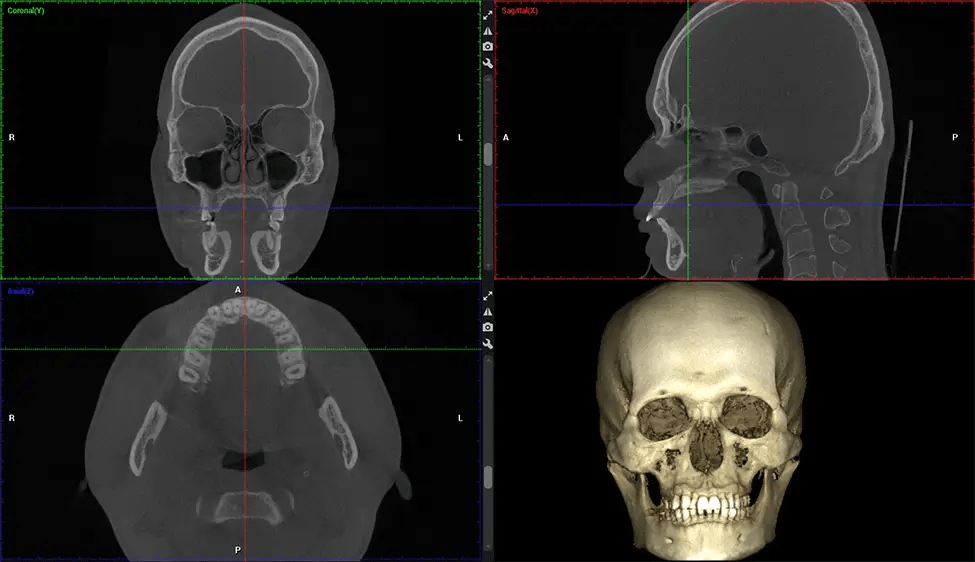

Cone Beam Computed Tomography (CBCT) is an advanced imaging technique used in dentistry and maxillofacial surgery to obtain detailed 3D images of the oral and maxillofacial structures. At Dr G Dental Studio, our CBCT scanners utilize a cone-shaped X-ray beam and a specialized detector to capture images from different angles. A computer then combines these images to create a 3D representation of the patient’s oral anatomy.

This 3D scan, called cone beam computed tomography, gives your dentist a more complete image of your oral anatomy and disease processes than a traditional X-ray. Unlike conventional X-rays, which capture a 2D image of your mouth from various angles, a 3D scan takes multiple digital X-rays for one image. It provides a complete view of your jaw, teeth, nerves, and soft tissues. This enhanced view allows dentists to detect minor issues not visible in traditional 2D scans, such as impacted wisdom teeth or bone fractures in the sinus cavity.

There are many benefits to using CBCT technology, especially compared to the traditional 2D X-ray format. One of the most significant advantages of CBCT scans is that they provide much more information than traditional X-rays. A scan lets your dentist see images from all angles of your jaw and mouth, including your sinuses, nasal cavity, cheekbones, and other surrounding areas. This added information helps your dentist craft a comprehensive treatment plan that addresses all aspects of your oral health.

The patient is first positioned in the CBCT scanner, which typically consists of a rotating arm that houses the X-ray source and a detector. The patient’s head is immobilized to ensure accurate image capture. The X-ray source and detector rotate around the patient’s head, capturing various X-ray images from multiple angles. As the X-ray source rotates, it emits the cone-shaped X-ray beam towards the detector. The detector captures the X-ray images, which are then processed by the CBCT software.

After the scanning process, the captured X-ray images are processed by the CBCT software, which applies algorithms to reconstruct a detailed 3D image of the scanned area. The software compiles these individual X-ray images and creates a digital 3D representation of the patient’s anatomy. The reconstructed 3D CBCT image can be viewed and analyzed by the dentist or radiologist. This image can be manipulated, rotated, and zoomed in or out to examine specific structures and evaluate the patient’s condition.